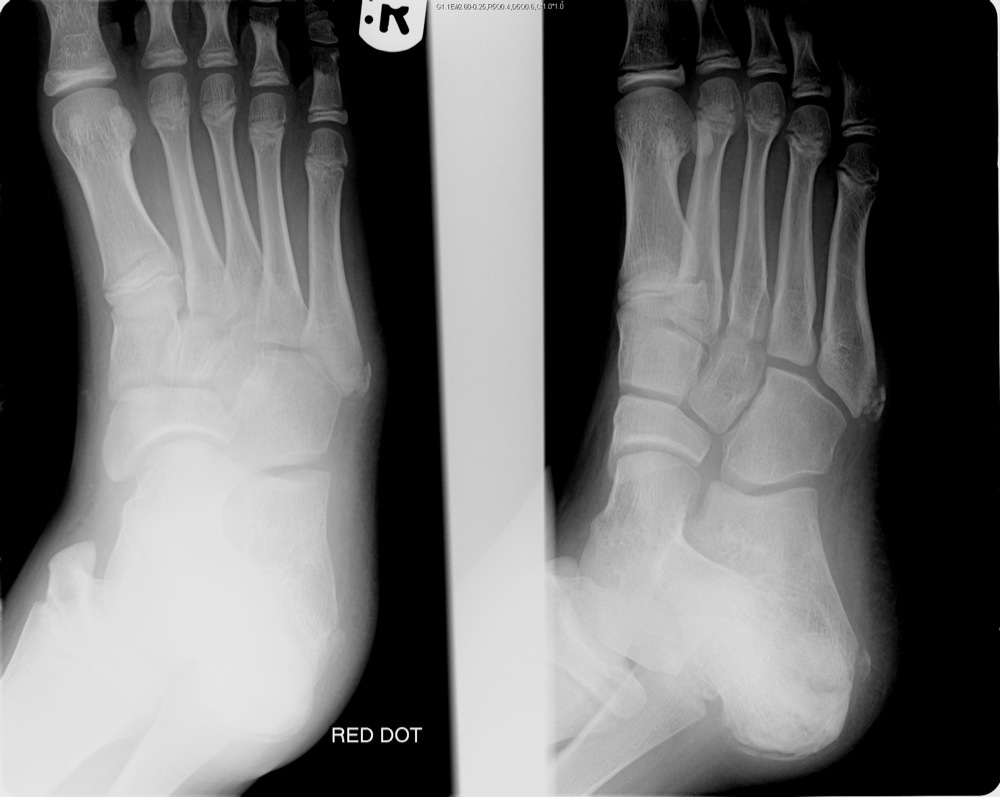

Анатомия суставов Шапарова и Лисфранка: фото и информация

Раздел: Мудрость в деталях